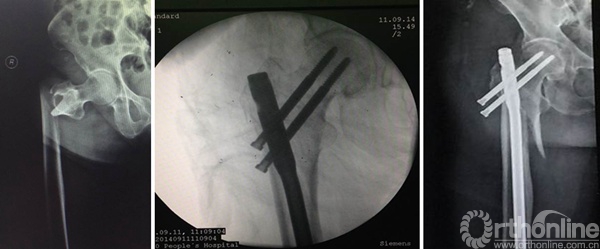

肖XX,男,35岁

术后

术后1年